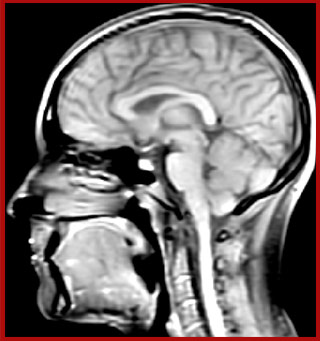

Dr. Rauscher says, “For MWI we perform 3D T2 with 32 or more echoes. This used to take a long time, but with Compressed SENSE we can decrease this to ten minutes for the whole head. Because of the large field of view (FOV) on the readout direction, we even get information from the brainstem, which we previously missed when we were using the GRASE approach. Having the whole head scan is nice because it has spatial resolution, orientation and FOV that are comparable to the standard 3D clinical MS scans, including the FLAIR and 3D T2, and a 3D T1 for brain volume.”

T1 - Weighted, Myelin Water Fraction Superimposed

MWI Spinal cord coverage

Spinal cord coverage

MWI Smaller, more isotropic voxels

Smaller, more isotropic voxels

MWI Excellent detail in quantitative maps

Excellent detail in quantitative maps

Images courtesy of Adam Dvorak, Department of Physics and Astronomy, University of British Columbia